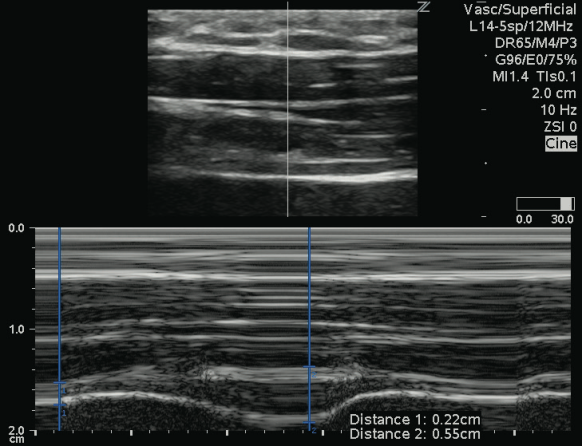

1)膈肌厚度(TDi)测量:膈肌厚度反映膈肌的收缩能力。采用高频线阵探头,置于患者右侧腋前线第810肋间(图1,获取图像(图2分别测量吸气末膈肌厚度(Tdi-insp)与呼气末膈肌厚度(Tdi-exp),重复测量3次取平均值,并计算膈肌增厚分数(DTF),公式为:

DTF =Tdi-insp - Tdi-exp/Tdi-exp×100%

2  膈肌厚度图像